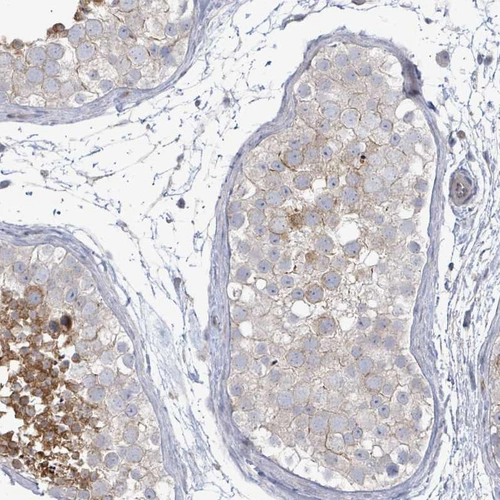

Immunohistochemical staining of human lymph node shows moderate to strong positivity in lymphoid cells.